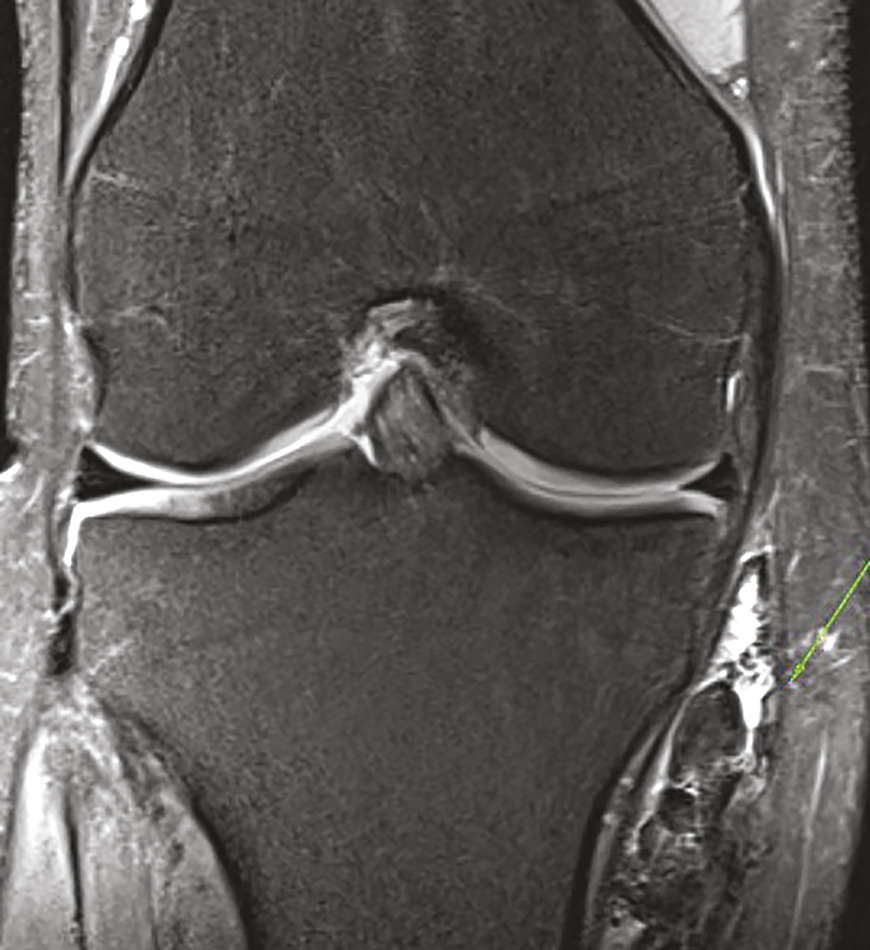

Ce jeune homme de 20 ans consultait pour une douleur du genou évoluant depuis 1 an initialement étiquetée bursite. Un traitement médical lui avait été prescrit pour cette affection. Devant la persistance de la douleur, une échographie était réalisée qui montrait une formation kystique atypique car mal limitée, à paroi épaissie et hyperhémique. Le caractère particulier de cette lésion amenait à prescrire une imagerie par résonance magnétique (IRM) qui montrait une infiltration évoquant une synovite villonodulaire en regard de l’insertion des muscles de la patte d’oie (fig. 1 et 2 ). La lésion était réséquée chirurgicalement et l’examen anatomopathologique notait une prolifération de cellules mononucléées ovoïdes ou comportant des inflexions fusiformes, associées à des histiocytes spumeux et du pigment hémosidérinique, sans atypie cytononucléaire ni activité mitotique, confirmant le diagnostic.